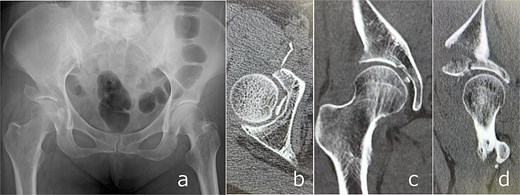

Plain radiographs demonstrated an anterior dislocation of the right hip with associated acetabular fractures (Fig. 1). Computed tomography (CT) after closed reduction revealed fractures of the anterior inferior iliac spine (AIIS), the anterior acetabular wall, and an intra-articular femoral head fracture fragment (Fig. 2). The injury was classified as Pipkin type IV [2] and Brumback type 4B [3].

Anteroposterior (a) and lateral (b) radiographs of the right hip obtained at initial presentation, demonstrating anterior hip dislocation associated with acetabular and anterior inferior iliac spine fractures.

CT images obtained at initial presentation: Axial (a), coronal (b), and sagittal (c) views, as well as three-dimensional reconstructions (d and e), showing anterior hip dislocation with fractures of the acetabular anterior wall and anterior inferior iliac spine.